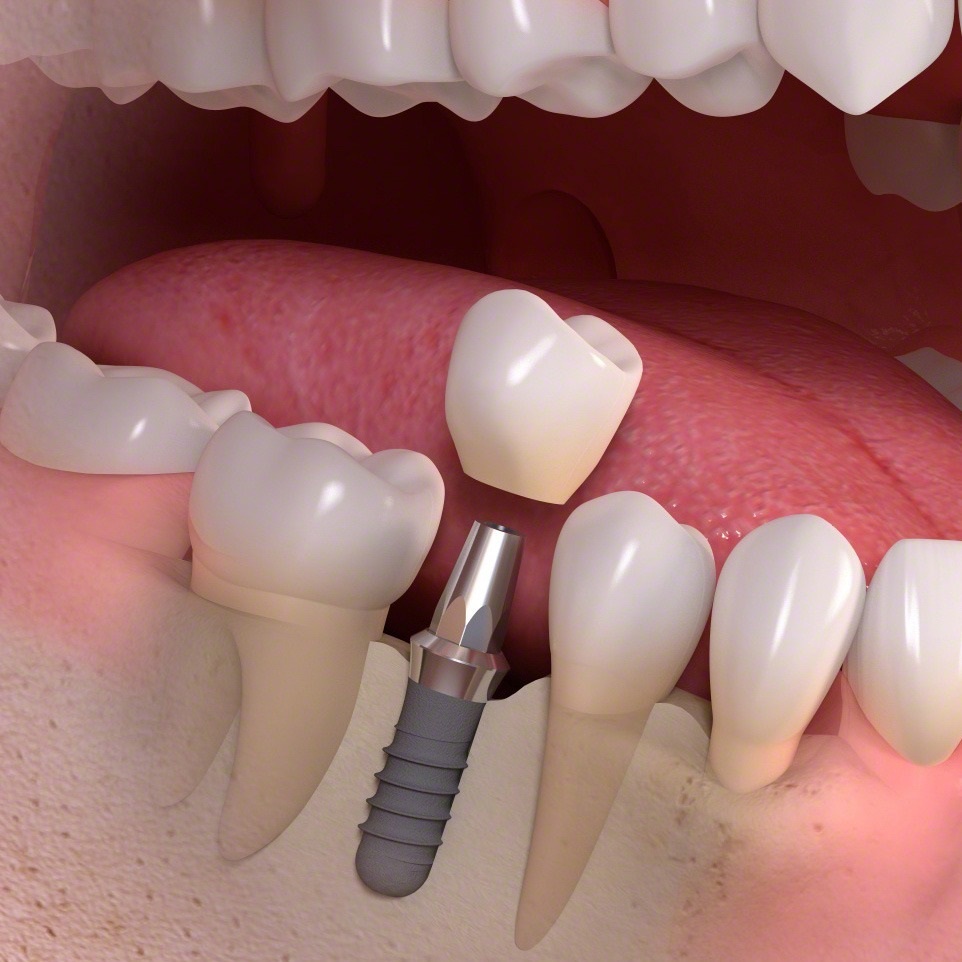

همانطور که در ابتدای مقاله عنوان شد، ایمپلنت دندان از سه بخش اصلی تشکیل شده که هر کدام نقش مهمی در جایگزینی دندان از دست رفته ایفا میکنند. پایه یا فیکسچر که شبیه یک پیچ کوچک است، درون استخوان فک قرار میگیرد و عملکردی مشابه ریشه دندان دارد و ثبات پروتز را فراهم میکند. روی فیکسچر قطعهای به نام اباتمنت نصب میشود که به عنوان رابطی بین پایه و پروتز عمل میکند و پروتز ایمپلنت را در جای خود نگه میدارد. پروتز که شامل روکش، بریج یا اوردنچر است، جایگزین تاج دندان یا دندانهای از دست رفته میشود و ظاهر طبیعی و عملکرد کامل دهان را بازمیگرداند. با کنار هم قرار گرفتن این سه بخش، ایمپلنت دندان امکان جویدن راحت، تکلم طبیعی و لبخندی زیبا را فراهم میکند.